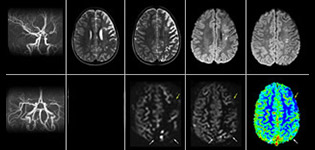

The value of susceptibility weighted imaging in visualizing brain injury is well documented. The Philips multi-echo SWIp technique provides fast susceptibility weighted imaging with enhanced susceptibility contrast and high resolution.

“Pediatric imaging is not without its challenges,” Dr. Miller says. “Since our patients are often very small, we need very high-resolution imaging. In cases of brain injury, we need to obtain information quickly so the treating clinicians can make decisions on care. We rely on high resolution and robust imaging capabilities, and SWIp provides that.”

“SWIp helps us identify blood or blood products, calcification, and diseases that affect the vascular system,” says Dr. Miller. “In children with traumatic brain injuries, it highlights areas that are injured, better than some of the previous techniques that we were using. These children often have micro-injuries that cause small amounts of blood or tissue damage. Adding SWIp helps us to better characterize the extent and nature of the injury. Having characterized an injury to the extent of what’s possible supports our diagnostic confidence.”

“I would definitely recommend other users to implement SWIp. We initially added the SWIp sequence following a lot of support for its utility in the literature. Then we directly compared SWIp to the 2D gradient echo sequences that we were using. After a good amount of clinical experience in seeing its benefits, we were confident to replace the old sequences with SWIp. It gives us a better assessment of the physiological processes of the brain that were less apparent on our previous imaging sequences,” says Dr. Miller. “SWIp is now a routine sequence for imaging traumatic brain injury patients at PCH, and it’s episodically added for patients who have intracranial vascular abnormalities.”

“I believe SWIp is rapidly becoming the standard in imaging traumatic brain injury, because of its high sensitivity to venous blood products. SWIp may even help attract patients; our neurosurgeons often ask to have the patients imaged on our scanners with highly sensitive techniques like SWIp. There’s also a growing application of SWI sequences in other vascular abnormalities because of the possibilities around physiological assessment of the brain than just a standard structural imaging.”